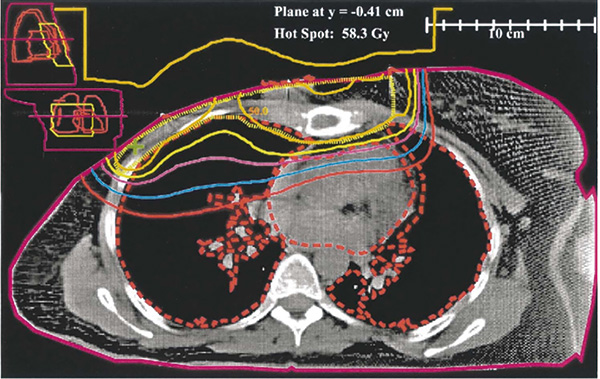

研究在172个国际中心开展,患者入组条件为单侧Ⅱ期、中等风险接受乳房切除术,无远处转移,切缘净距至少1毫米。患者按照1∶1随机分配至放疗组和非放疗组,随访每年一次持续10年,有需要的情况下行对侧乳房X光检查,研究主要终点为总生存期。

最终放疗组808例,非放疗组799例,中位随访时间为9.6年。总体而言,84.8%的患者接受化疗,78.7%接受内分泌治疗,19.8%接受曲妥珠单抗治疗。研究期间,放疗组发生150例死亡,总生存率81.4%,无放疗组145例,总生存率81.9%,风险比1.04,无显著差异。

共计29例患者出现胸壁复发,放疗组9例(1.1%),非放疗组20例(2.5%),绝对差不足2%,虽风险比达0.45,但研究者认为事件数较少、置信区间宽,这一差值不太可能转化为具有临床意义的生存获益。放疗组的无病生存率为76.2%,非放疗组为75.5%,风险比0.97;远处转移无病生存率分别为78.2%和79.2%,风险比1.06。

根据淋巴结状态、年龄、分子亚型进行亚组分析,也未观察到放疗对总生存率和其他次要终点的影响。三阴性乳腺癌患者胸壁放疗后总生存率较非放疗组降低,风险比1.91。研究中胸壁复发事件较为罕见,其他研究数据也给出同样结论:在采用包含多种治疗手段的现代治疗方案后,局部复发的发生率很低。在这种情况下,胸壁放疗很难显著降低死亡率。